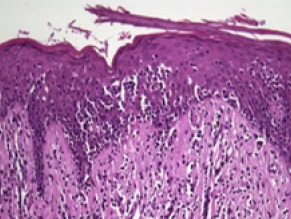

Mycosis fungoides (MF) is due to the neoplastic proliferation of mature CD4+ T cells that infiltrate the skin.

Histology of mycosis fungoides (MF) is characterized by malignant infiltration of neoplastic-T-cells in the epidermis that are known as Pautrier microabscesses.